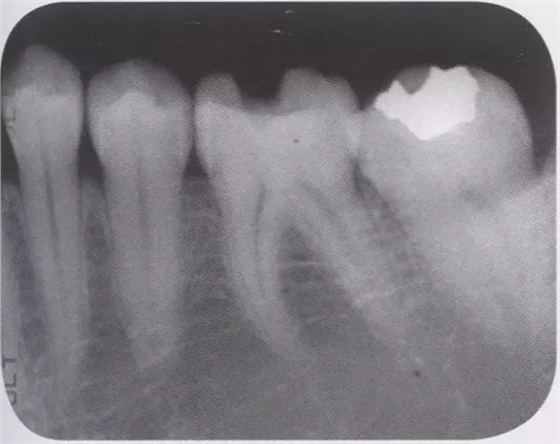

1、嵌體和高嵌體 在磨牙區(qū)域,由于牙齒近中面以及遠(yuǎn)中面的傾斜程度不同,常會(huì)遇到分離困難的病例。例如,智齒的近中根傾斜,引起鄰牙根間隙過窄的情況。相鄰牙齒的近中傾斜,牙冠進(jìn)入被處理牙倒凹處的情況(圖2、3)。以上情況,鄰接面由于齲齒形成窩洞,即便是運(yùn)氣好在齦下做了分離,也會(huì)因?yàn)槌鲅斐扇∧@щy、頰舌的成形變大。所以采取以下處理措施。 1、術(shù)前拍攝牙片,根據(jù)牙根的傾斜判斷有沒有引起鄰牙根間隙過窄的情況。若沒有傾斜,就是簡(jiǎn)單病例。 2、若智齒沒有對(duì)合牙,也考慮拔除智齒。 3、鄰接面用樹脂填充之后,用間接法進(jìn)行烤瓷嵌體或烤瓷高嵌體修復(fù)。 1、貼面治療 對(duì)于變色牙齒進(jìn)行貼面治療的情況下,牙頸部觀察無變色的情況下,可直接在齦上做成形。普通成形深度能夠保存牙釉質(zhì),因而判斷為簡(jiǎn)單病例。(圖4) 如果牙頸出現(xiàn)變色,就需要進(jìn)行齦下成形,難度增加。如果也存在前突問題,為改善變色貼面不能做厚,因而難度會(huì)更高。如果希望糾正前突、改善變色,則需要增加切削量,甚至可能進(jìn)行拔髓。另外,由于粘接對(duì)象主要是牙本質(zhì),因而需要格外注意。

圖1 智齒向遠(yuǎn)中傾斜病例

圖2智齒嵌入被處理牙鄰接面的倒凹,即便分離成功,成形范圍也會(huì)變大。